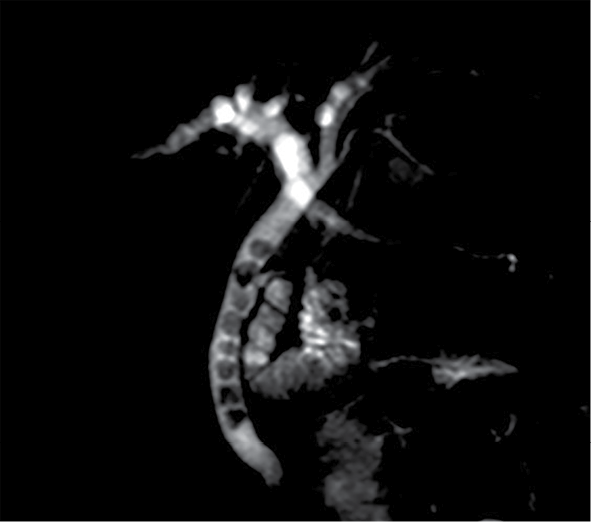

Paciente del sexo masculino de 87 años con dolor abdominal de 1 semana de evolución localizado en el mesogastrio, sin irradiación, escala visual analógica (EVA) 8/10; negó nausea, vomito o fiebre. Ingresó al servicio de urgencias, donde se solicitaron los estudios de imagen que se muestran en las figuras 1, 2 y 3.

3. Los hallazgos señalados en la figura 2, ¿en qué estructura anatómica se encuentran?

a) Conducto colédoco.

b) Conducto hepático común.

c) Conducto cístico.

d) Conducto pancreático principal.